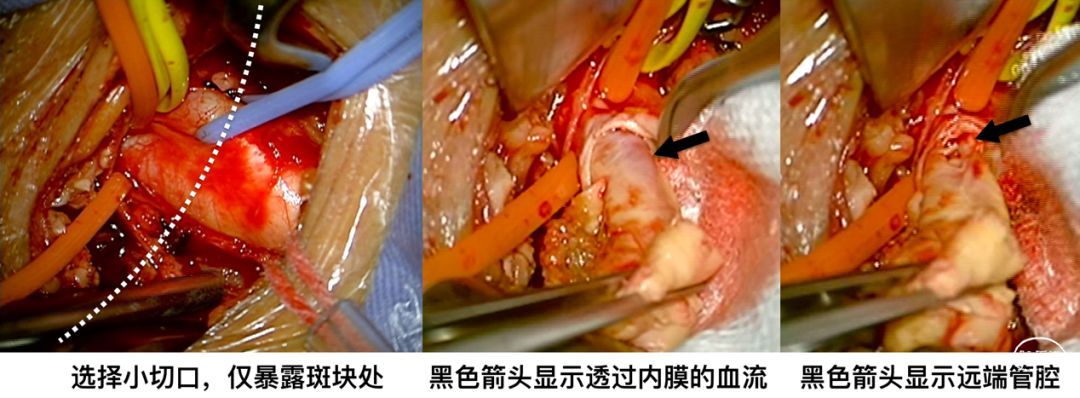

我们本就备着复合手术,所以先复查造影看看,还是闭塞。但我选择相信我们无敌的超声团队,果断小切口,打开后触及斑块远端比较软。远端先切开外中膜,保留内膜完整,透过半透明的内膜可见远端管腔内的血流,鲜红色而非血栓的黑色,看来我们的选择是对的![]() 。

。

果然,在剪开内膜后,管腔内很干净、没有血栓、有返向的血流。按照常规进行剥脱,复查造影再看——通畅的,虽然有负性重构,但等一两周就可恢复正常![]() 。

。